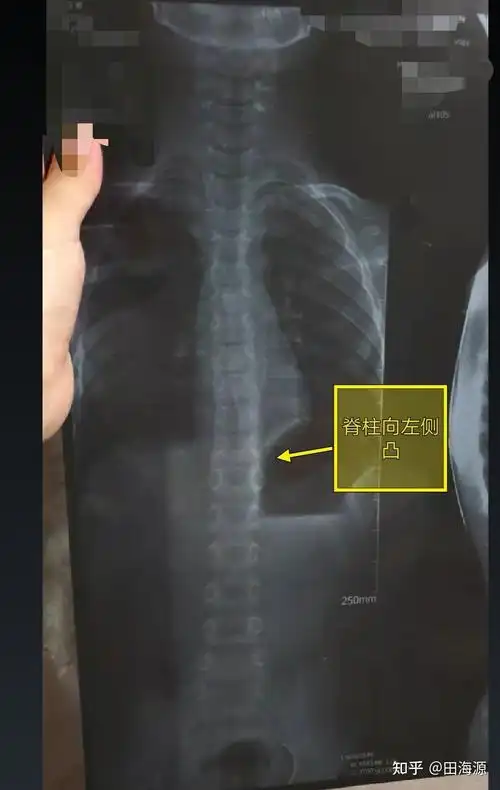

分享一个76度脊柱侧弯改善案例希望可以帮到有需要的朋友